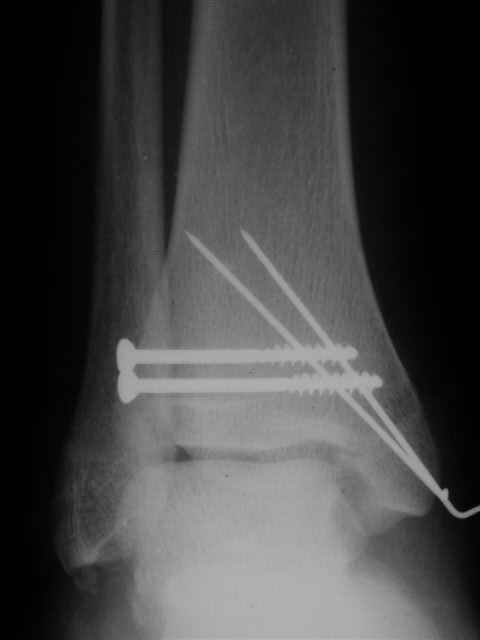

> интересуюсь тактикой лечения повреждений голеностопного сустава.

Ничего сверхъестественного, но если есть интерес, то в понедельник пересниму Рг-граммы и отправлю.

Я предупреждал, что ничего сверхъестественного. Каюсь, что одна из спиц прошла несколько дальше, чем нужно было, но главное - перелом стабилизирован и больной работает суставом в полном объёме, несмотря на представленную раннее травму коленного сустава.